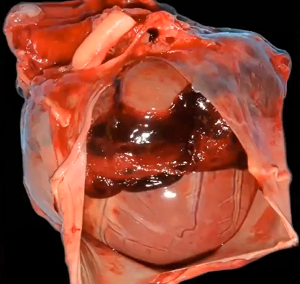

Chordae may fail due to elongation, rupture, thickening, retraction, or calcification. Mitral valve prolapse (MVP) may cause the valve's chordae tendineae to stretch. In the final stages, the valve's chordae tendineae sometimes rupture, and if they are major chords, causing the valve to collapse completely. Rarely, a cavalier's mitral valve's major chordae tendineae may suddenly rupture earlier in the progression of the disease, before any enlargement of the heart takes place.

MVP may cause the valve's chordae tendineae to stretch. In the final stages, the valve's chordae tendineae sometimes rupture, and if they are major chords, causing the valve to collapse completely. Rarely, a cavalier's mitral valve's major chordae tendineae may suddenly rupture earlier in the progression of the disease, before any enlargement of the heart takes place.